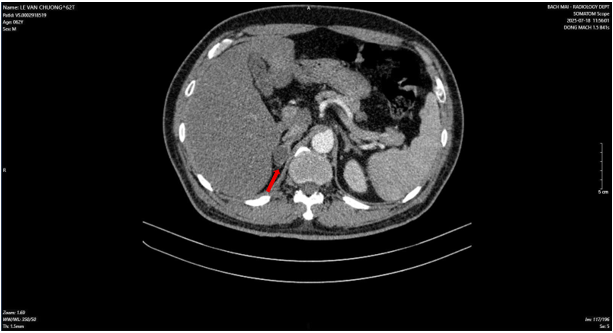

Bệnh nhân được chụp cắt lớp vi tính vùng tiểu khung, phát hiện khối u tại thùy phải của tuyến tiền liệt. Sau đó, bệnh nhân đã được chụp phim cộng hưởng từ nhằm đánh giá chính xác tính chất khối u (Hình 1).

Hình 1: Hình ảnh nốt vùng chuyển tiếp lệch phải (PIRADs 3) trên phim cắt lớp vi tính (mũi tên đỏ) và trên phim cộng hưởng từ (mũi tên vàng).